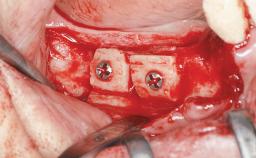

Autologous Block Graft and Guided Bone Regeneration (GBR) for Horizontal Ridge Augmentation in the Posterior Mandible

An 18-year-old man was referred for implant therapy in the posterior mandible to the Department of Oral Surgery and Stomatology (University of Bern, Switzerland). He was healthy and did not smoke. Tooth 35 was congenitally missing, involving a single-tooth edentulous space that offered an adequate mesiodistal dimension for implant placement but exhibited a typical pattern of buccal flattening. A panoramic radiograph was obtained, which revealed a sufficient vertical bone height above the mandibular canal and a normal bone structure in the edentulous area.

Bone Augmentation Horizontal|Staged

Augmentation Materials Autogenous chips|Autogenous block(s)|Xenogenous|Membrane